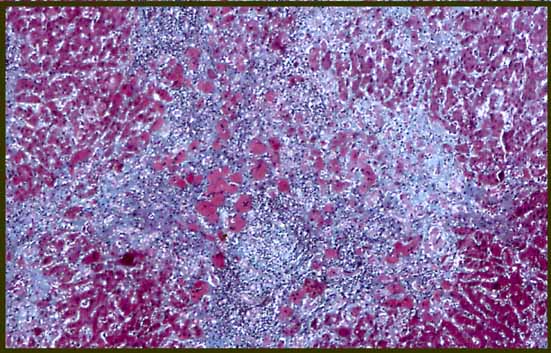

fig. 7

Figura 7.- HE 100X; hígado no cirrótico con una vena central (flecha izqda), y un acúmulo linfoide (flecha dcha).